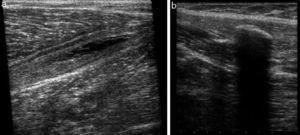

Durante esta fase de readaptación se realizan estiramientos progresivos combinados con trabajo activo (aumento de la intensidad de las contracciones musculares de isométricas a excéntricas) sin dolor (Figura 5).

Figura 5. Déficit en la visualización del defecto fibrilar exacto en estudios de RM y ecografía. a) Coronal T2 STIR rotura músculo-tendinosa de la cabeza larga del bíceps femoral que interesa el tendón común (flechas). Se observa retracción de fibras (punta de flecha) y edema intramuscular en pluma (*). No se objetiva defecto fibrilar con exactitud. b) Rotura miofascial de la cabeza medial del gastrocnemio medial (flechas). Estudio ecográfico en eje largo. Se observa retracción de fibras (flechas) y colección líquida miofascial (*), pero no se objetiva con exactitud el defecto fibrilar.GM: gastrocnemio medial. S: sóleo.